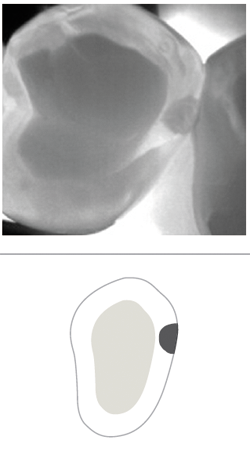

The handpiece tip has two soft flanges with NIR lights and a camera for capturing images (Fig. 1). Simply place the tip over the occlusal surface so that the flanges hug the buccal and lingual/palatal aspects of the teeth (Fig. 2) to view live video of teeth (Fig. 3). I can capture an image in one second with a squeeze on the wand. I can also capture short video clips using a “rocking” technique that actually creates a 5-second video of the tooth seen at varying directions instead of just a static image.

Fig. 2 Fig. 3